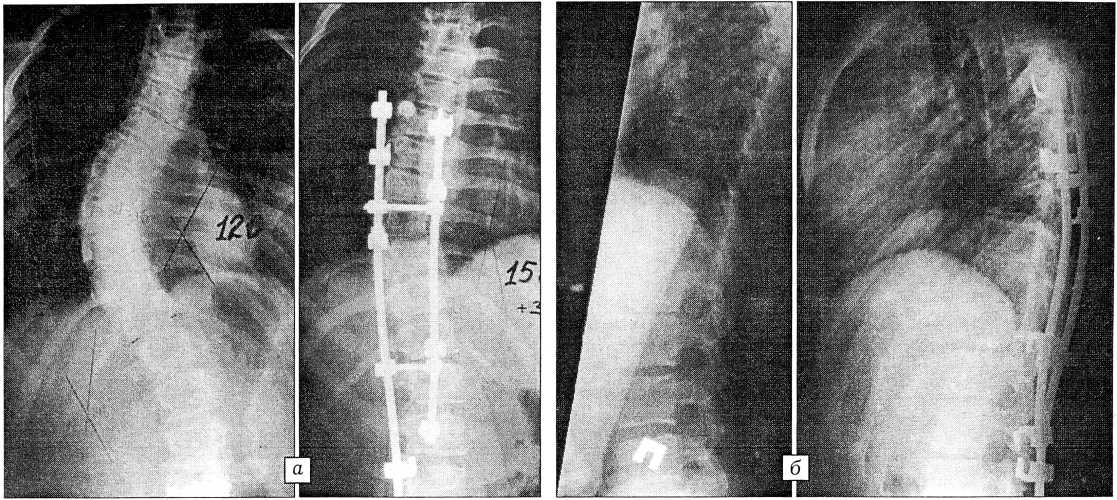

Наименьшая коррекция — 20 и 25 была получена у 2 пациентов, которым ранее проводилось хирургическое лечение в других клиниках с использованием в одном случае дистрактора Харрингтона, в другом —конструкции Красноярской клиники. Результат оказался неудовлетворительным, и пациенты поступили в нашу клинику со сформировавшимся задним спондилодезом. Наибольшая коррекция (от 40 до 56°) отмечена у 9 больных с тяжелыми формами сколиоза (рис. 3).

Рис. 3. Рентгенограммы больной Т. 13 лет с диспластическим правосторонним грудным сколиозом IV степени до и после операции — торакотомии, дискэктомии Т6-7, Т7-8, Т8-9, Т9-10, коррекции деформации тремя стержнями системы CD с транспедикулярной фиксацией. а — прямая проекция: достигнута коррекция общего угла 60°, угла противодуги 26°; б — боковая проекция: до операции грудной кифоз усилен (90°), после операции коррекция грудного кифоза 30°, поясничный лордоз сохранен.

Результаты лечения в сроки от 6 мес до 1 года прослежены у 8 больных. Потеря коррекции общего угла и утла противодуги в пределах 10° отмечена в 3 случаях у пациентов с большим потенциалом роста. В остальных случаях потери коррекции не выявлено. У одного больного произошло вывихивание верхнего крюка с вогнутой стороны деформации из-за перелома дуги позвонка, что повлекло за собой потерю 70% достигнутой коррекции. Больной был повторно оперирован: произведен частичный перемонтаж металлоконструкции с установкой двух крюков. Достигнуто восстановление 80% исходной коррекции (34°).